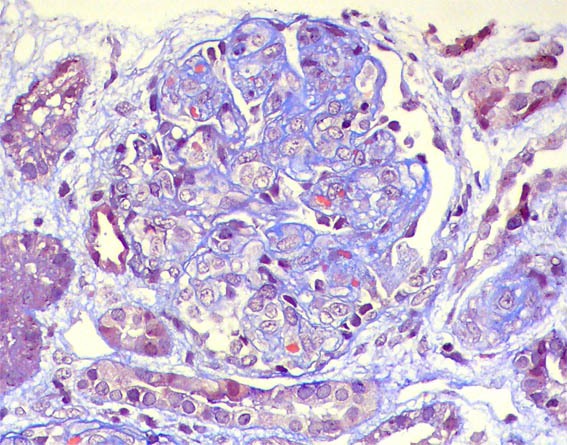

Se hace biopsia renal. Observe las imágenes.

Figura 6. Tricrómico de Masson, X400.